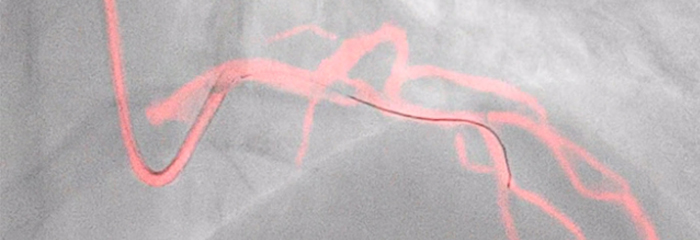

À medida que mais pacientes com CAD são considerados para terapia de intervenção minimamente invasiva, o planeamento de tratamento ideal é prejudicado pelo facto de a angiografia coronária 2D ter limitações na deteção e avaliação da estenose coronária. Os dados não são ligados de forma consistente e significativa antes e durante o procedimento, o que acrescenta tempo e complexidade ao planeamento de tratamento. Concebemos as nossas soluções de cardiologia para superar estes desafios, para que possa perceber os benefícios da eficiência clínica no laboratório de cateterismo:

A terapia guiada por imagens, iFR, IVUS e monitorização hemodinâmica, bem como o planeamento pré-procedimento cardíaco e aplicações avançadas, estão todos ligados à interface de terapia guiada por imagens para permitir a visualização, manipulação e configuração personalizada no monitor a partir de um único controlador ao lado da mesa ou a partir da sala de controlo.